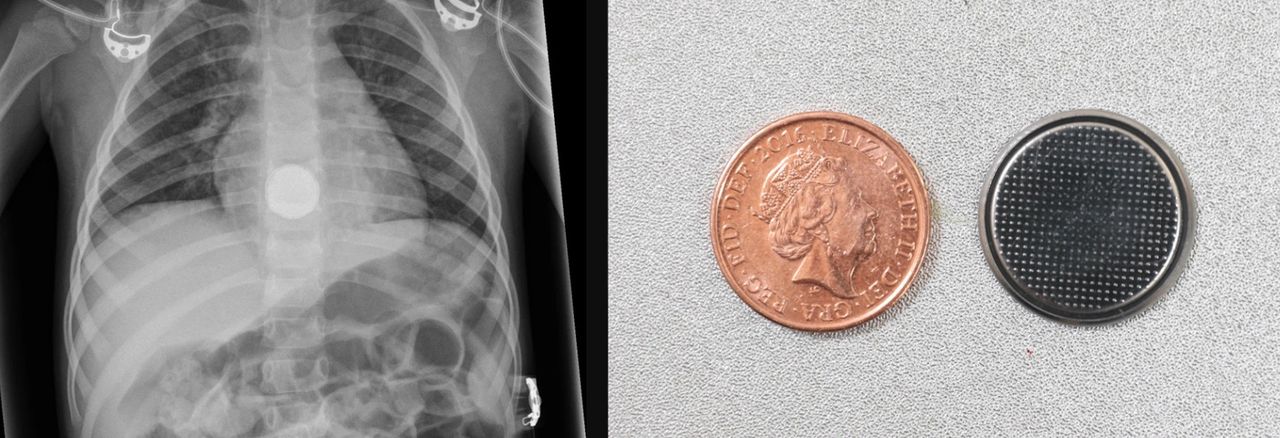

Przeprowadzenie badań obrazowych małych dzieci i niemowląt wiąże się z wieloma wyzwaniami. Od strachu przed nieznanymi maszynami, cierpieniem, które sprowadza małego pacjenta do szpitala po trudności z utrzymaniem go w nieruchomej pozycji.

Jest to szczególnie istotne w przypadku zdjęć rentgenowskich, ponieważ jeśli wyjdą niewyraźne, trzeba je powtórzyć. To z kolei w przypadku małych dzieci jest niewskazane ze względu na promieniowanie.

Na szczęście ryzyko poruszenia się można ograniczyć dzięki urządzeniu, które w ostatnim czasie podbiło serca internautów na całym świecie. Pigg-O-Stat ma na celu uniemożliwienie dzieciom poruszania się podczas badania.

"Pigg-O-Stat to uniwersalne urządzenie do unieruchamiania dzieci, przeznaczone do pozycjonowania niemowląt i małych dzieci do odpowiedniego prześwietlenia bez znaczących komplikacji" – informuje producent.

Mimo że urządzenie to powstało w latach 60. XX wieku, wiele osób dowiedziało się o nim stosunkowo niedawno. Rodzice maluszków wymagających prześwietlenia klatki piersiowej mają bowiem dużo więcej zmartwień niż robienie im zdjęć podczas badania.

Mimo to radiolodzy zaznaczają, że urządzenie to jest zbawienne, a praca staje się o niebo łatwiejsza. Dziecko trafia do urządzenia na kilka minut, wcześniej na badanie każdy musiał przeznaczyć nawet kilkadziesiąt.